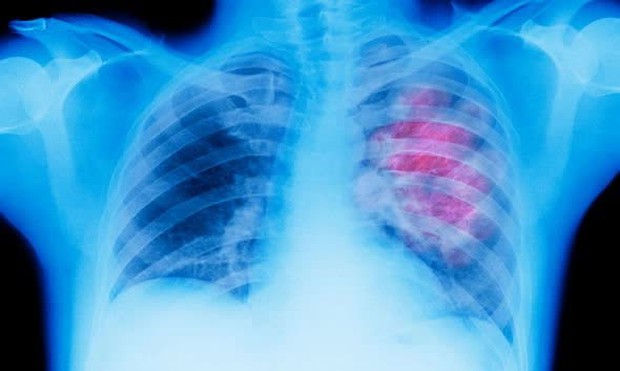

Ung thư phổi là sự tăng trưởng không bình thường của các mô trong phổi. Trong giai đoạn sớm, ung thư phổi thường không có triệu chứng rõ ràng, do đó, nhiều người chỉ phát hiện bệnh khi nó đã ở giai đoạn nặng. Một số triệu chứng thường gặp ở bệnh nhân ung thư phổi bao gồm: ho trở nặng hoặc kéo dài; khàn tiếng; khó thở; đau ngực liên tục; ho ra máu; mệt mỏi kéo dài; mắc các bệnh nhiễm trùng phổi thường xuyên, như viêm phổi; giảm cân không rõ nguyên nhân...

Ung thư phổi là một trong những loại ung thư phổ biến và nghiêm trọng nhất. Theo thống kê của tổ chức GLOBOCAN năm 2020, Việt Nam ghi nhận tổng cộng 26.262 trường hợp ung thư phổi. Đây là loại ung thư xếp thứ hai về tỷ lệ mắc cho cả nam và nữ. Tỷ lệ mắc mới ở Việt Nam là khoảng 23 trường hợp/100.000 dân, còn tỷ lệ tử vong là 21,9/100.000 dân. Tuy nhiên, nếu được tìm ra và phát hiện các triệu chứng của bệnh ngay từ giai đoạn đầu, điều này sẽ gia tăng cơ hội sống sót cho bệnh nhân.